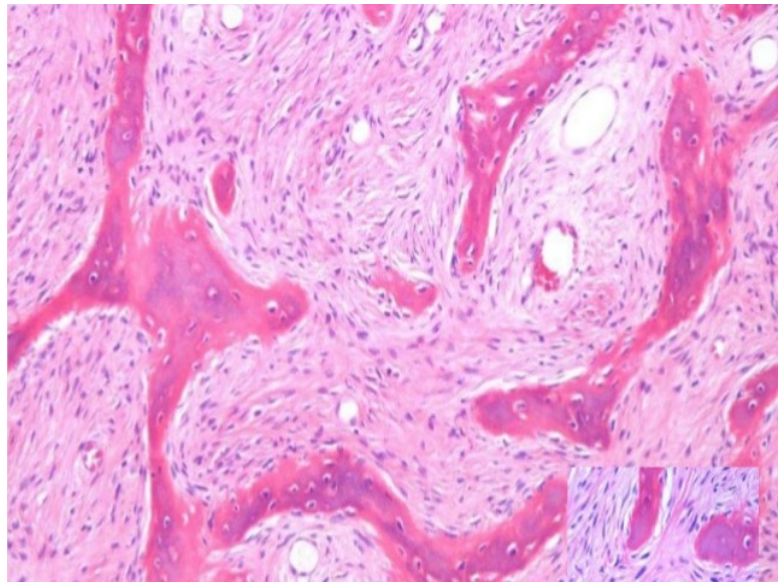

19.患者主訴左下顎牙齦輕微腫脹且第二大臼齒動搖,黏膜表面完整,根尖放射線檢查如附圖一,切片檢查發現 如附圖二中所示,下列何者為最佳之診斷? (A)棘皮瘤性造釉細胞瘤(ameloblastoma, acanthomatous type) (B)慢性牙周炎(chronic periodontitis) (C)骨內鱗狀細胞癌(intraosseous squamous cell carcinoma) (D)鱗狀齒源性腫瘤(squamous odontogenic tumor)